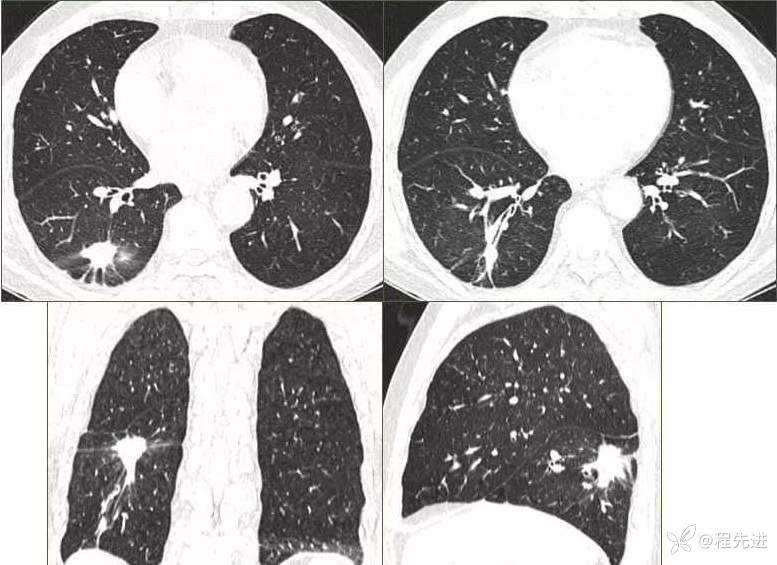

CT

肺窗